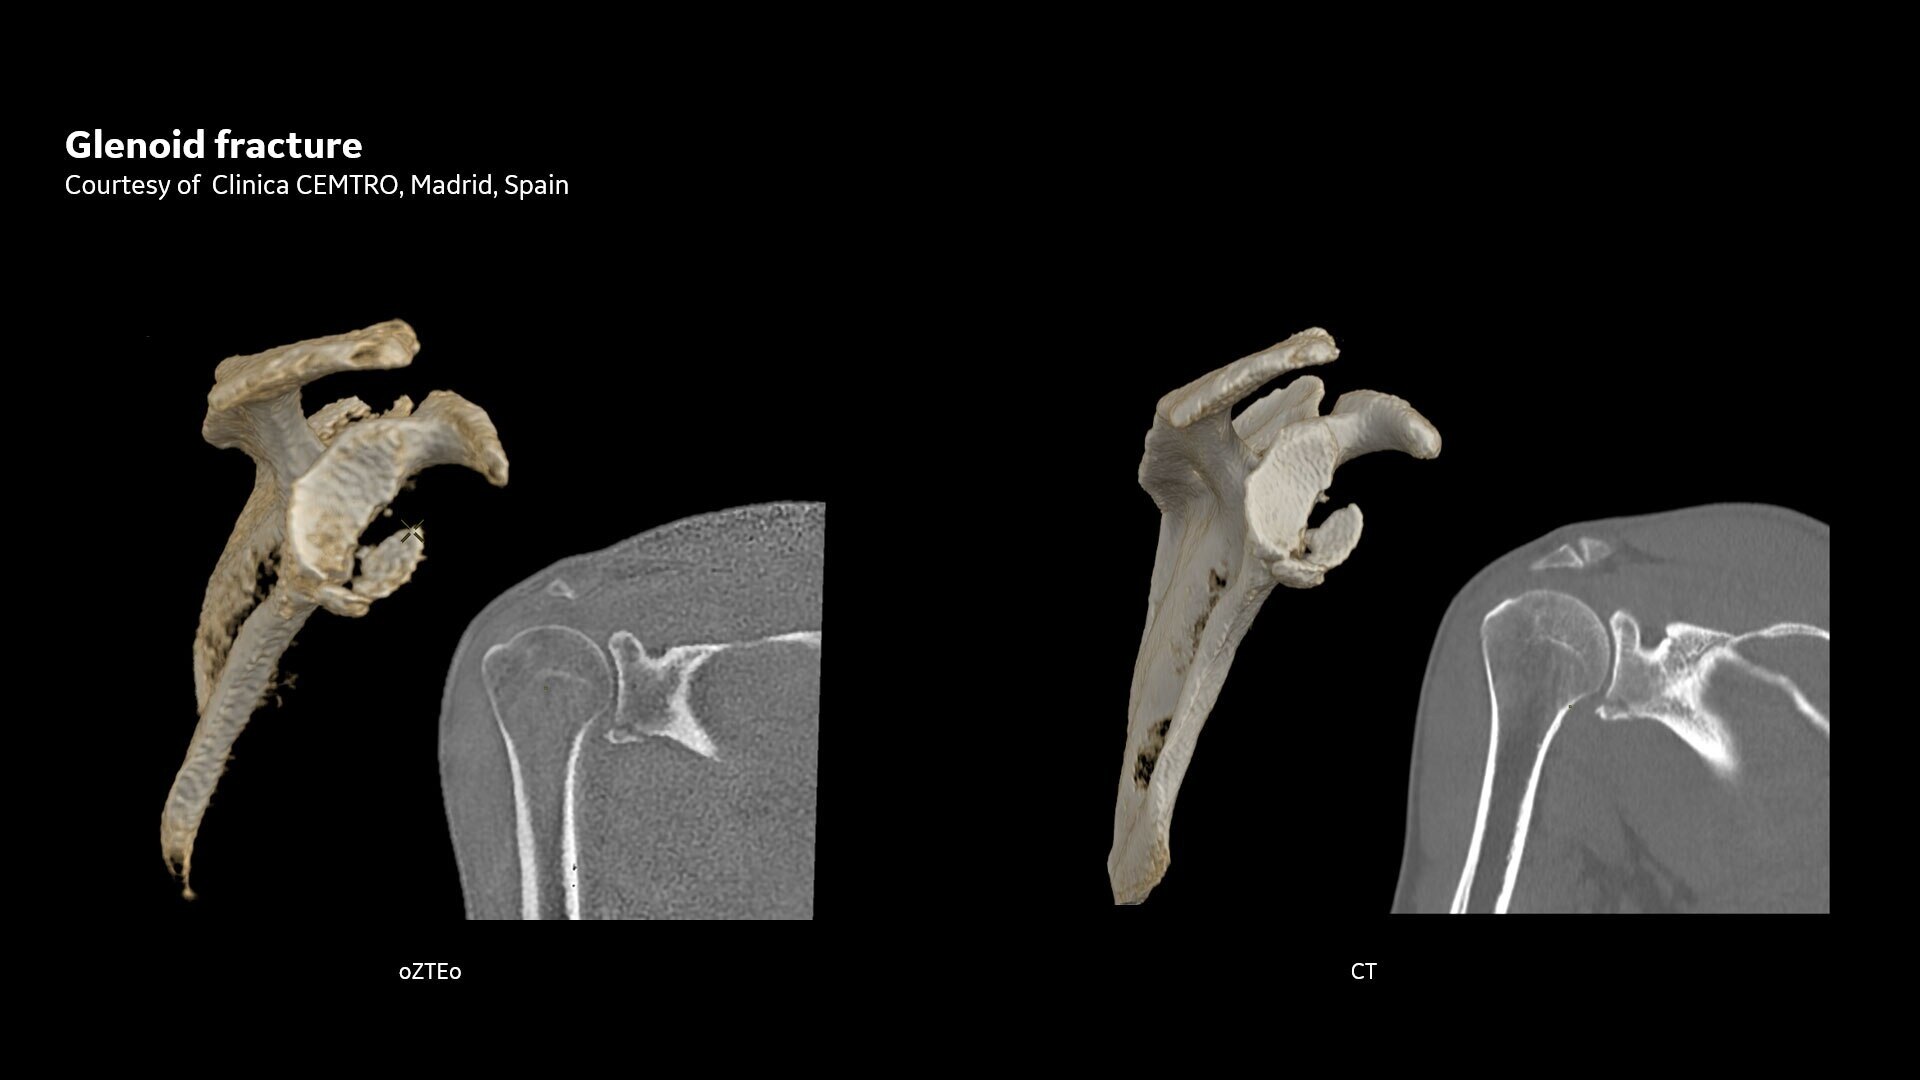

Available for all anatomies without ionizing radiation, oZTEo delivers images of bone morphology, calcification, ossification and fractures. oZTEo complements conventional MR soft tissue exams with perfect co-registration and provides 3D isotropic imaging using a radial ZTE acquisition, with inherent motion insensitivity. Use oZTEo with Volume Illumination for realistic 3D rendering.